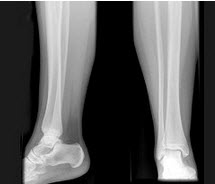

40、单项选择题

女,35岁,左侧外踝可扪及一硬结,有轻压痛,结合影像学检查,最可能的诊断是()

A.骨瘤

B.骨软骨瘤

C.骨巨细胞瘤

D.骨肉瘤

E.骨样骨瘤